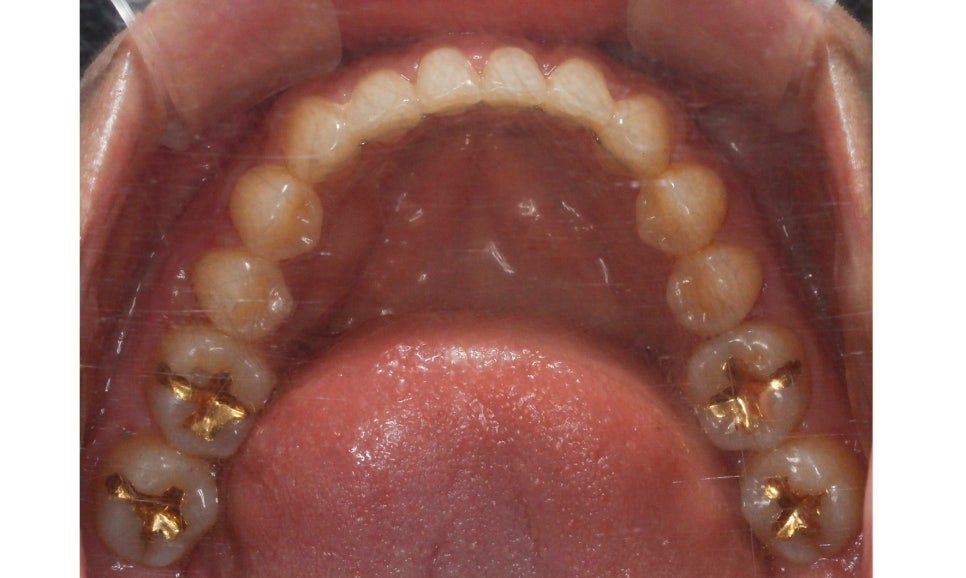

상악 교합면 사진입니다.

사진에서 우측 측절치가 설측으로

들어와 있어서 전치부

치열이 삐뚤거리는 모습인데요,

이러한 경우 들어와 있는 측절치를

원래 위치로 빼내기 위해서

주변 치아들을 이동시켜 공간을 만들어 주어야 합니다.

교정 초기에 이 부분에 open coil spring이

(공간확보 용)결찰될 수 있습니다.

상악 교합면도 교정 후 가지런하게 바뀐 모습입니다.